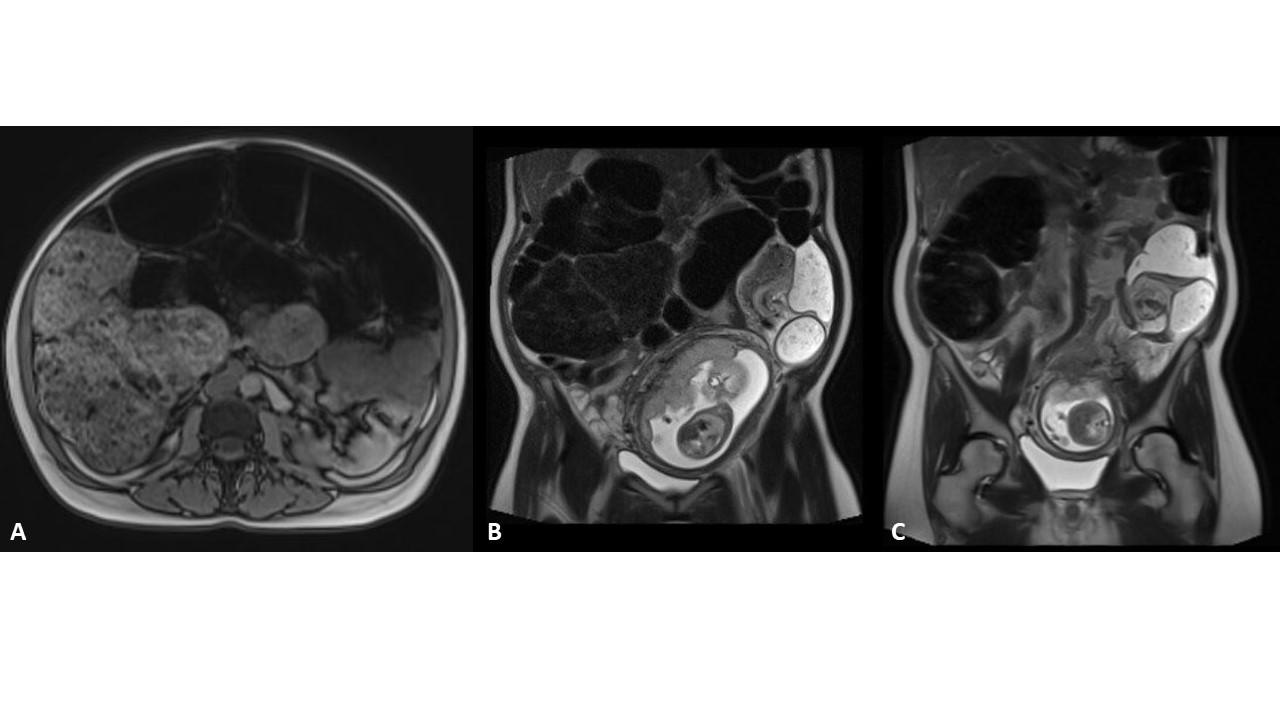

A 40-year-old pregnant woman presented with acute constipation and abdominal distention. A sigmoid volvulus was diagnosed (Figure 1). There was a transition point in the sigmoid colon with a “mesenteric swirl sign” (Figures 1B, 1C).

Colon decompression tubes are used for other conditions such as Ogilvie’s syndrome and megacolons. In this case we used a Marcon colon decompression set (see below, Figures 2 and 3). This tube-set is particularly practical and useful as it comes with a wire and the tube has a pigtail end. This pigtail configuration prevents damage to the mucosa or colon perforation once the tube has been placed and is left inside. In addition, the tube has many side holes that allow for passage of liquid stool and air (Fig. 1 and 3D).